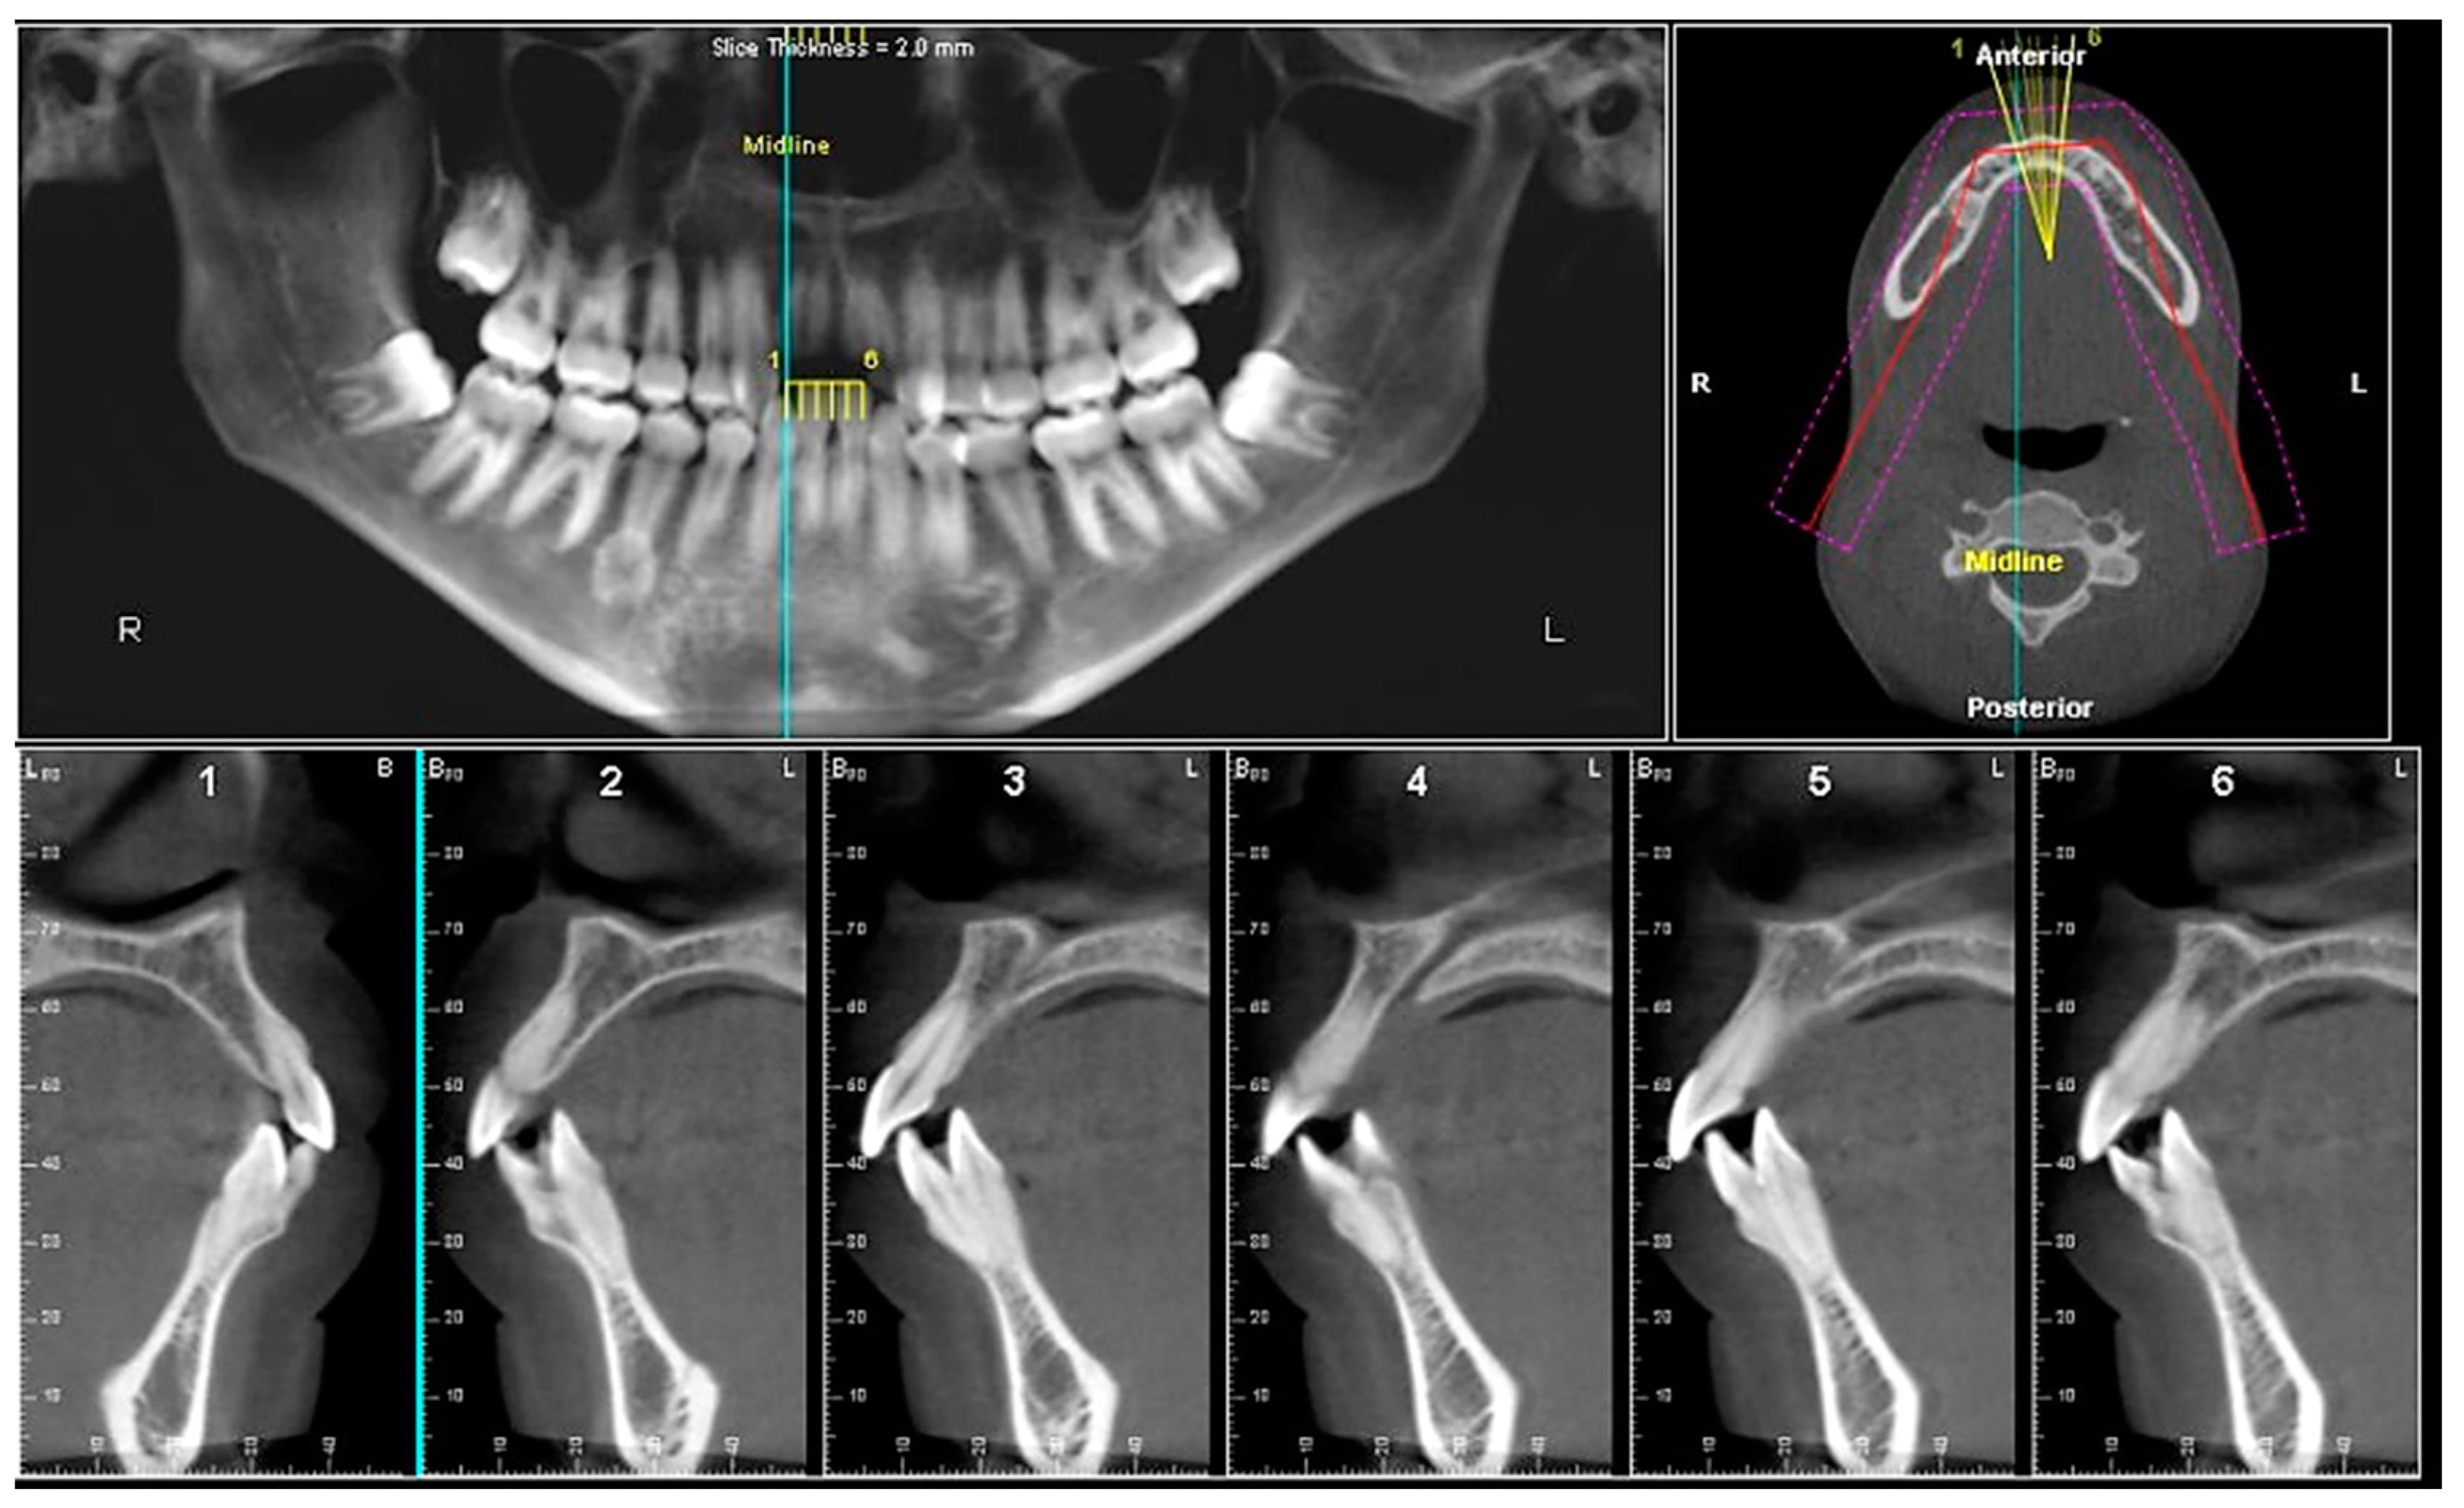

- Assessment of an impacted canine with close proximity to the lateral incisor. Figure 27 shows photographs and a panoramic radiograph of a case in which there is an impacted permanent maxillary right canine in an unfavorable position, a missing mandibular left second premolar and uncoordinated dental midlines. The relationship of the impacted canine to the adjacent lateral incisor cannot be determined from the conventional 2D radiograph. Therefore, CBCT was acquired. Figure 28 shows CBCT images, including coronal, sagittal, axial views, and volume rendering, which demonstrated close proximity of the impacted canine to the lateral incisor, and an area of bone loss buccal to the crown of the impacted canine. Before acquisition of CBCT, the tentative treatment plan was to extract the maxillary right first premolar and bring the canine to the dental arch. However, due to the findings presented by CBCT, the treatment plan was altered in favor of extracting the impacted canine, a clinical decision that was strongly favored by the patient. In this case, the first premolar would substitute for the canine. The maxillary left first premolar and mandibular right first premolar were also extracted. Therefore, each quadrant would have one missing tooth by end of treatment. Orthodontic post-treatment photographs are presented in Figure 29. Figure 30 shows a post-treatment 2D panoramic radiograph. CBCT was neither necessary nor indicated at completion of orthodontic treatment, and therefore only a conventional 2D panoramic radiograph was taken.